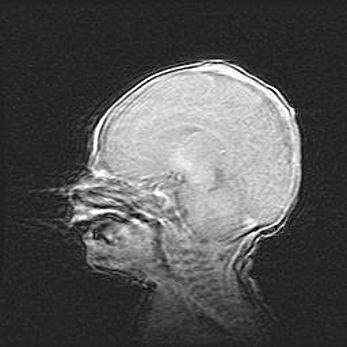

Церебральная ишемия II.

Возраст: 5 дней

Вес: 3400 г

Пол: женский

Окружность головы: 35 см

Срок гестации: 39 недель

Церебральная ишемия – это заболевание, характеризующееся недостаточностью (гипоксией) либо полным прекращением (аноксией) снабжения мозга кислородом по причине закупорки одного или нескольких сосудов. Это приводит к  что метаболическим расстройствам различной степени тяжести в тканях головного мозга, развитию коагуляционных некрозов и гибели нейронов.